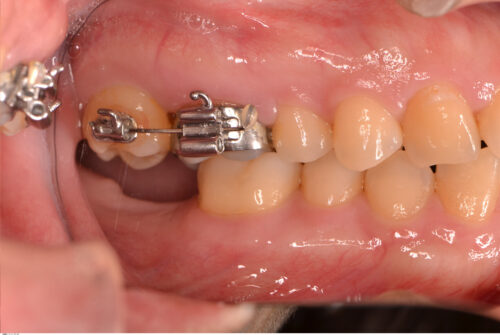

30代女性。矯正歯科にて全額矯正を行った際、下顎7番の長期欠損による上顎7番の挺出も改善。最終的に欠損部をどうするかという話になり、矯正医からインプラント治療を勧められ当院に来院された患者さんです。

下顎7番にインプラントを埋入。